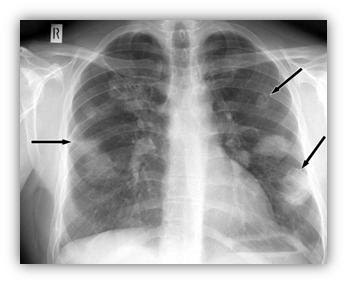

Radiografía de neumonía

Niño de 5 años con síndrome de condensación pulmonar y resolución de la neumonía a los 10 días.